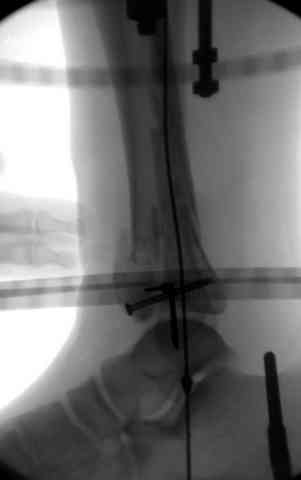

Снова приветствую вас, коллеги. К моменту вступления в обсуждение аксакалов, операция была, увы, выполнена(31.10.07.) Начали с доступа к наружной лодыжке, произвели ее фиксацию спицами, развернули кусок заднего края, наложили дистрактор, затем произвели дистракцию, фиксацию спицами дистального эпиметафиза б/бк,Рентгено-контроль. синтез наружной лодыжки 1/3пластиной. из двух коротких разрезов сформирован канал под медиальную тибиальную пластину LCP. Края ран ушиты без натяжения. Прочувствовать жесткость фиксации винтами с угловой стабильностью не удалось, поэтому дистрактор оставлен на энное время.

На представленных R-снимках не окончательный вид после остеосинтеза. Дистальная опора давила на стопу, пришлось ее сместить проксимально, в рез-те чего, она закрыла щель сустава, последние снимки не информативны.